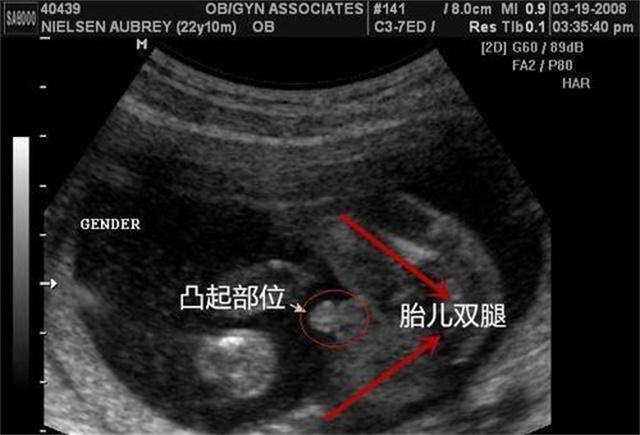

Face à ce défi, les professeurs Yang Zhen et Lv Zhilai de l'université de médecine traditionnelle chinoise de Pékin se sont engagés à participer à la bataille par le biais du microblogging. Il est rapporté que les deux parties discutent actuellement du programme spécifique du défi, initialement prévu pour être assisté par 32 femmes en âge de procréer pour participer au test, le challenger et le participant avec un rideau de tissu entre les participants dans le test, seulement basé sur les résultats du diagnostic du pouls pour déterminer la grossesse de la participante.

Les mères enceintes sont sans doute les plus qualifiées pour s'exprimer dans ce débat. De nombreuses femmes enceintes affirment que le test de grossesse par pouls est un "test psychologique" et qu'elles font davantage confiance aux tests médicaux modernes tels que les tests d'urine et l'échographie.

"Allez-vous diagnostiquer si vous êtes enceinte grâce au pouls de la médecine chinoise ?" Hier, le journaliste a mené une enquête simple dans le groupe QQ de Guangzhou sur l'accouchement des mères de deuxième enfant. Au total, 63 mères du groupe ont accepté l'enquête, mais lors de leur première ou deuxième grossesse, aucune d'entre elles n'a eu recours à la médecine traditionnelle chinoise pour diagnostiquer la grossesse par le pouls. Les mères ont déclaré qu'en général, lorsqu'elles constatent que les règles n'arrivent pas, la première réaction est d'utiliser un test de grossesse pour savoir si elles sont "touchées". "Les tests de grossesse sont bon marché, très précis et, surtout, pratiques, et peuvent être achetés en pharmacie. Pour déterminer le résultat, il faut se rendre à l'hôpital pour effectuer un test d'urine formel et constituer un dossier pour consulter un médecin". Huang Yi, mère de deux enfants dans le district de Yuexiu, a déclaré.

Les mères ont également déclaré que la raison pour laquelle elles n'ont pas eu recours à la médecine chinoise pour confirmer le diagnostic était qu'elles pensaient que la médecine chinoise était basée sur la seule expérience et que le taux de précision n'était pas élevé. La médecine occidentale utilise des moyens technologiques de détection et les résultats sont plus précis. En outre, l'échographie, les tests sanguins, etc. permettent également de déterminer s'il s'agit d'un "bébé à problèmes" ; en termes relatifs, les résultats de la médecine occidentale sont directs, précis et permettent de gagner du temps.

Deng Bo a également déclaré qu'il est certain que, que ce soit dans les hôpitaux chinois ou occidentaux, dans le diagnostic de la grossesse dans les critères cliniques, il n'y a pas de "diagnostic du test de grossesse par pouls", l'étalon-or pour le diagnostic de la grossesse étant de trois : test d'urine, tests sanguins et échographie.